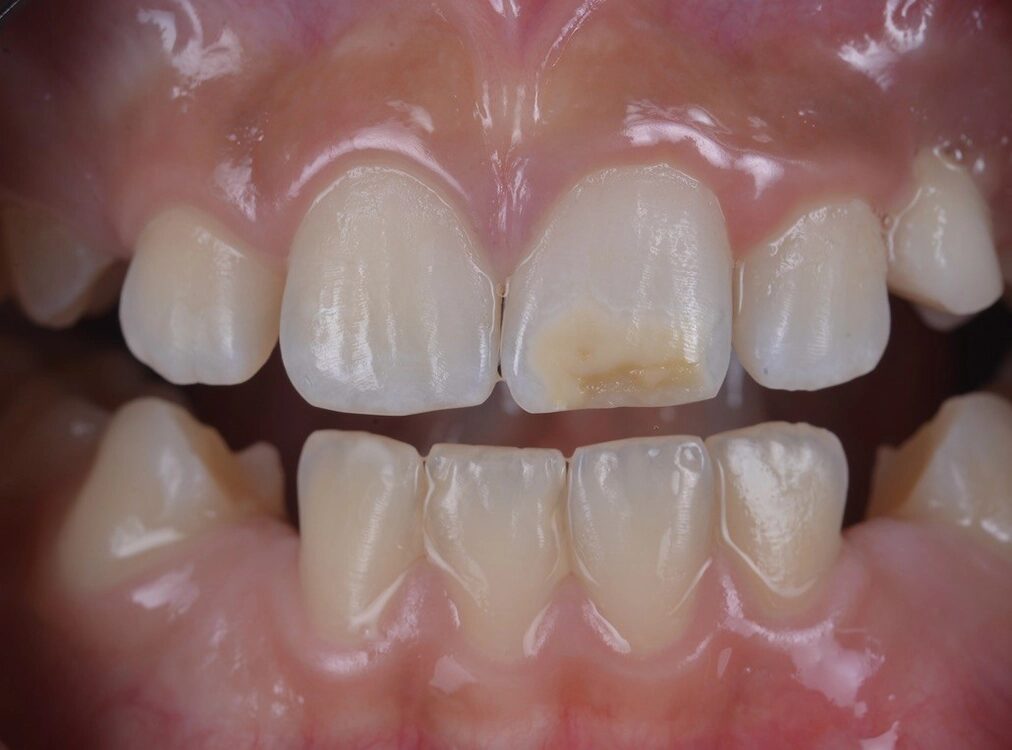

MIH-Läsionen an den Frontzähnen manifestieren sich häufig als klar abgegrenzte Opazitäten, deren Farbpalette von Weiß über Creme und Gelb bis hin zu Braun reicht. Diese farblichen Veränderungen sind ein wichtiger diagnostischer Hinweis auf die zugrundeliegende Strukturstörung des Zahnschmelzes. Besonders auffällig ist, dass die Intensität der Färbung mit dem Grad der Porosität und der strukturellen Beeinträchtigung des Schmelzes korreliert: Je dunkler und ausgeprägter die Opazität erscheint, desto höher der Restproteingehalt im Zahnschmelz, und desto höher ist das Risiko für posteruptive Substanzverluste, Frakturen und Hypersensitivitäten (Abb. 1). Die sorgfältige Beurteilung dieser visuellen Merkmale ist daher von zentraler Bedeutung für die Planung einer individuellen und effektiven Therapie, die sowohl funktionelle als auch ästhetische Aspekte berücksichtigt.

![Abb. 2: Klinisches Fallbespiel [17]: a) Klinischer Ausgangbefund bei einem 12-jährigen Patienten,](https://dentalwelt.spitta.de/wp-content/uploads/2026/04/Abb2_A-1024x707.webp)